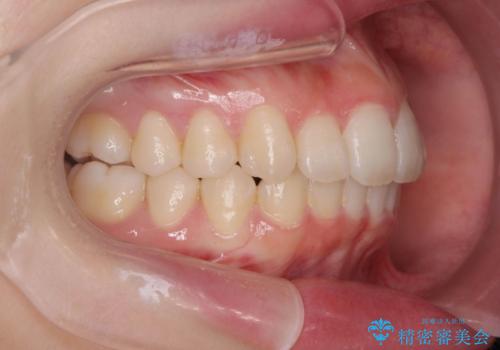

口腔内の清掃状態の良さに加えて、マウスピースを毎日きっちりと装着し、しっかりと使用していただけたことからワイヤー矯正は行わずにきれいに歯並びを治すことができました。

途中顎位が変わり、マイクロインプラントを併用した上顎臼歯の遠心移動が必要となったため治療が長期化しました。